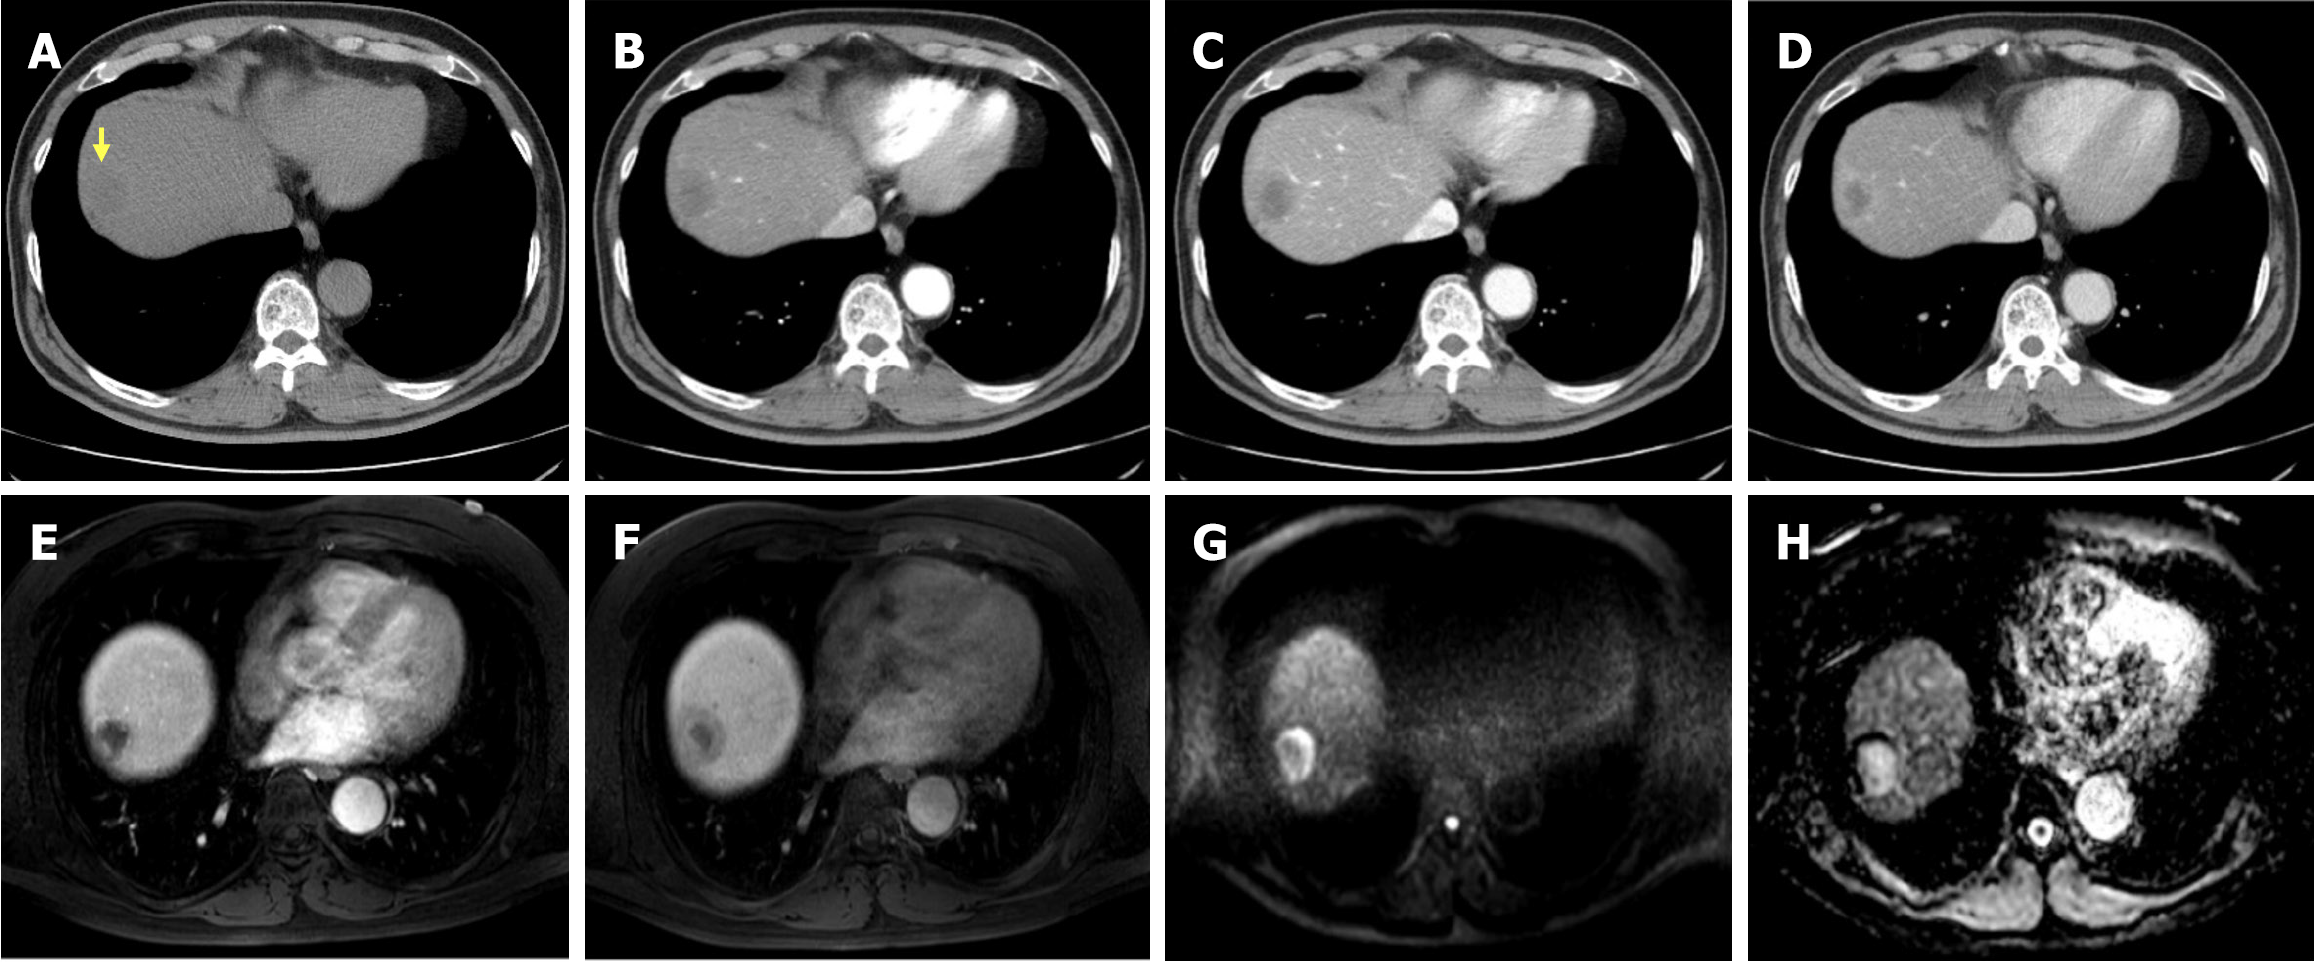

Abdominal contrast-enhanced CT and MRI demonstrated a 3 cm centripetal enhancing lesion located in the right hepatic dome, raising the suspicion of a malignant lesion such as cholangiocarcinoma or recurrent RCC metastasis. The lesion exhibited ill-defined margins without any evidence of major vessel invasion or distant metastasis (Figure 1).

Based on imaging findings, a 3 cm liver mass was identified in segment 8 (Figures 1 and 2), with no evidence of distant metastasis to the abdomen or chest. Based on these findings, a radical resection was performed. Considering the advantages of minimally invasive surgery, a laparoscopic right anterior sectionectomy was performed.